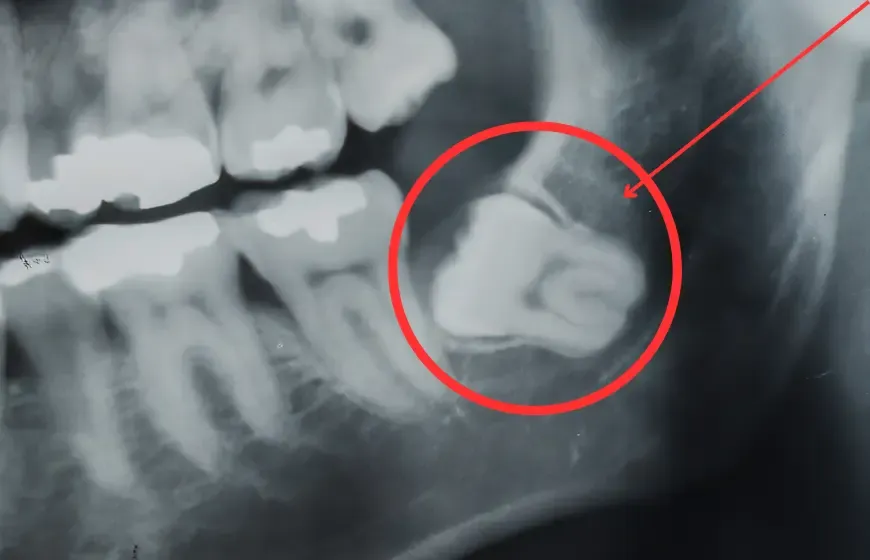

- Zęby zatrzymane lub częściowo wyrznięte: Ósemka może utknąć pod dziąsłem lub kością, co prowadzi do bólu, obrzęku i stanu zapalnego zwanego pericoronitis.

- Uszkodzenie sąsiednich zębów: Nieprawidłowo wyrzynająca się ósemka może naciskać na siódemkę, prowadząc do resorpcji jej korzenia lub powstawania próchnicy w trudno dostępnym miejscu.

Nie, nie każdy człowiek posiada zawiązki zębów mądrości, a ich brak jest całkowicie normalny i nie świadczy o żadnej anomalii. Jeśli jednak ósemki zaczynają sprawiać problemy, kluczowa jest konsultacja ze stomatologiem. Na podstawie zdjęcia RTG (najczęściej pantomograficznego) jestem w stanie ocenić ich położenie, stopień rozwoju i potencjalne ryzyko. W wielu przypadkach, aby uniknąć poważniejszych komplikacji, zalecam ekstrakcję, czyli usunięcie problematycznych zębów mądrości.